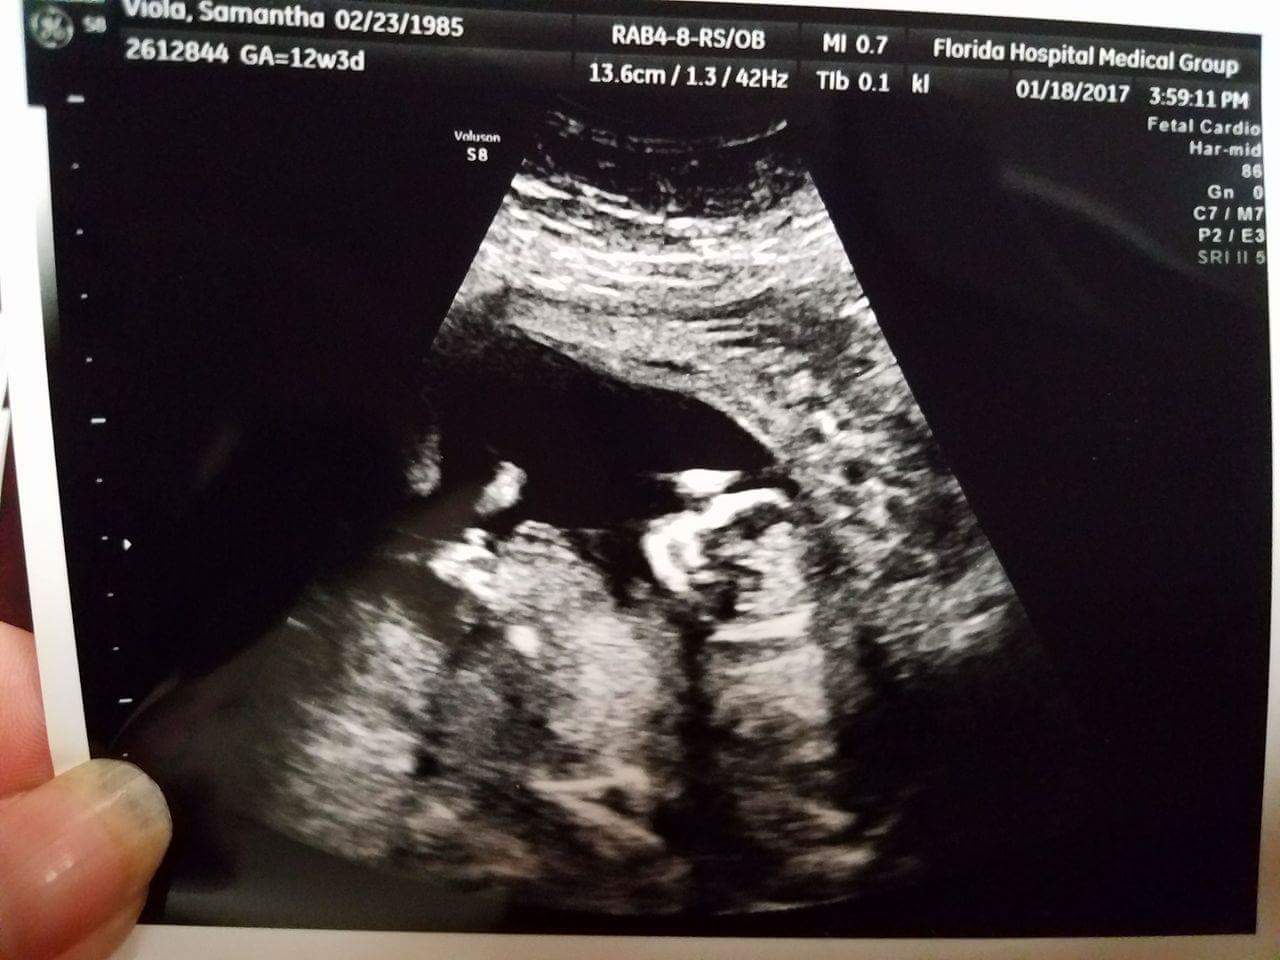

Help! The little one was very wiggly but I'm hoping someone can give me some sort of guess. I was 12w5d I think but they had me measured at 13w5d.

Oh geez, those last two pics look kinda girly...I'm not sure what to think now...:worry:

Oh, now I'm torn! The recent ones make me think girl. Any more?